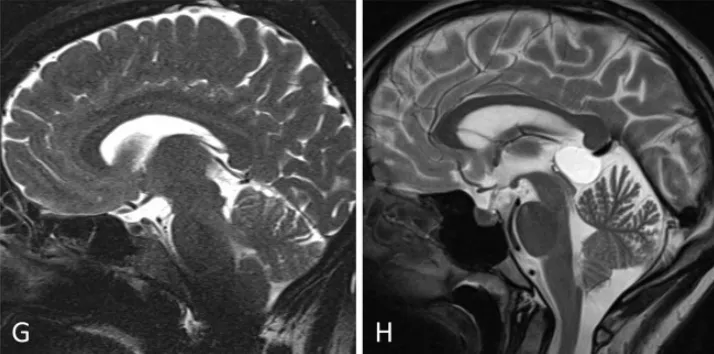

术前(A)及术后(B)正中矢状位MRCISS成像显示:松果体囊肿导致中脑导水管狭窄(箭头标示),但未引发脑积水。术后影像(B)证实囊肿完全切除,中脑导水管恢复通畅。开颅手术范围延伸至横窦区域(箭头标示)。患者临床症状完全消失。手术入路选择基于增强T1加权磁共振成像(冠状位D、E,轴位F)评估:左侧优势静脉窦及桥静脉分布情况,最终选择静脉窦穹隆较高的右侧入路。小脑幕倾斜度分析表明:旁正中入路(G)至松果体区的视角轨迹较中线入路(H)更为平缓。